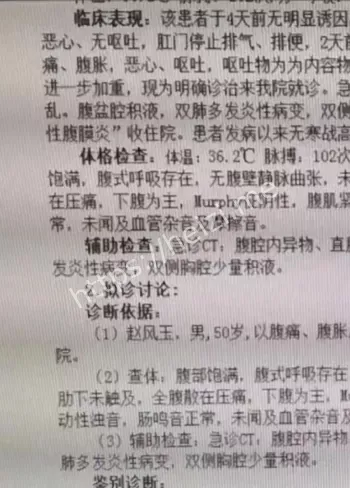

重点来了,这茄子可不是一般的茄子,30cm长,卡在直肠里,取出来可费了医生老大劲!据说大叔疼得满头大汗,医生也是满脸问号,手术室里气氛一度尴尬到爆。网友们在网上吵翻了,有人好奇“咋塞进去的”,有人直呼“这操作太野了”!还有人脑洞大开,猜是不是大叔在家做啥“实验”失败了? 直肠藏30cm茄子这关键词,绝对是热搜榜的潜力股。网友们一边吃瓜一边吐槽,纷纷表示这事儿太离谱,简直刷新认知底线。但说真的,这背后到底是啥情况?

医院操作引关注:医生的心理阴影有多大?

再说说医院这边,医生们估计也是满头黑线。据爆料,急诊科接到这病例时都懵了,手术过程小心翼翼,硬是把30cm茄子给取出来了!有网友调侃:“医生这波操作,心理阴影面积得有几平米吧?”还有人感慨:“医护人员太不容易了,啥病例都得面不改色!”这事儿也让大家好奇,医院咋处理的?会不会有官方通报? 深夜急诊、奇葩事件这些关键词,直接戳中吃瓜群众的兴趣点。医院的处理方式也成了讨论焦点,有人猜大叔会不会被医院“拉黑”,也有人关心后续医疗费用咋算。